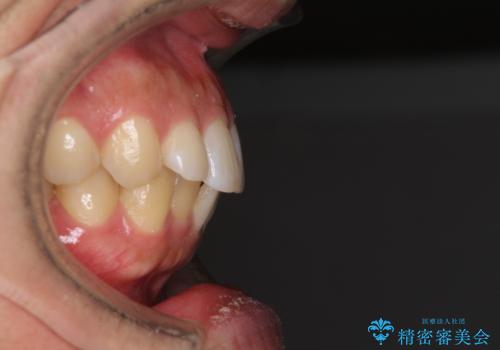

前歯のデコボコと突出感 インビザラインにて矯正治療

- 上下前歯のデコボコを気にして来院された患者様です。

インビザラインによる上下歯列の側方拡大と後方移動、IPR(歯と歯の間を削る)にるスペースの獲得により歯列を整えることとしました。

左上の小臼歯は捻転が強く、あえて180逆向きの状態で終了させる治療計画としました。